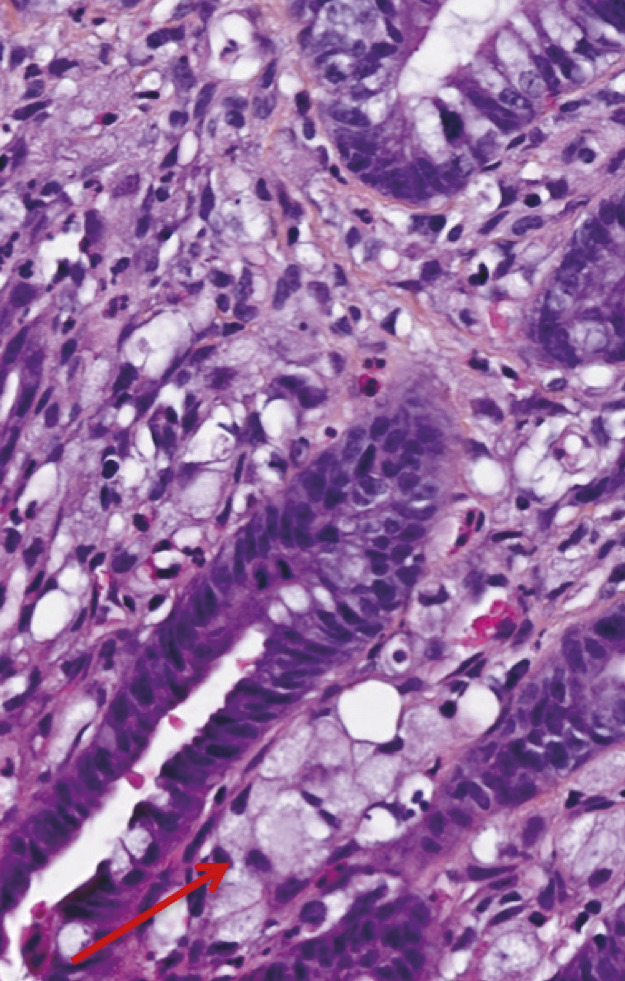

Un mois et demi plus tard, devant la persistance des symptômes et la perte de 6 kg supplémentaires, une tomodensitométrie est réalisée, qui montre un aspect épaissi de la paroi gastrique mesurant 17 mm d’épaisseur, limité à l’antre gastrique. Une nouvelle endoscopie œsogastroduodénale est alors réalisée, qui ne note pas d’anomalie évidente, si ce n’est toujours un aspect rigide à l’insufflation. Une écho-endoscopie haute est réalisée, qui révèle un épaississement localisé de la paroi gastrique et permet des biopsies guidées qui décè- lent la présence d’un adénocarcinome gastrique avec présence de cellules indépendantes.

Il faut savoir répéter l’exploration endoscopique en cas de persistance de symptômes dyspeptiques et de signes d’alarme. En effet, si la sensibilité de l’endoscopie pour les adénocarcinomes de type lieberkühnien est excellente, elle est moins bonne dans les linites gastriques qui peuvent être ignorées. De plus, les biopsies sont volontiers négatives dans les linites, avec une sensibilité de 50 % uniquement,1 incitant à réaliser des biopsies multiples (minimum 8) en cas de suspicion de cancer, et éventuellement des biopsies en puits, des macrobiopsies ou surtout une ponction-biopsie guidée par l’échoendoscopie.

De même, une confusion fréquente est faite entre le type histologique ADCI et la linite gastrique. Cette dernière est définie macroscopiquement, en anatomopathologie, en endoscopie (fig. 2) ou en imagerie (fig. 3), par un aspect épaissi et rigide de la paroi gastrique. L’aspect de linite est fréquemment associé au type histologique ADCI, comme cela a été noté dans une série de 27 linites gastriques analysées par deux anatomopathologistes différents. P armi ces linites, 21 étaient des adénocarcinomes gastriques à cellules indépendantes et 6 d’autres types histologiques selon la classification de l’OMS. Après une troisième lecture des lames, il apparaissait que 4 tumeurs avaient un contingent minoritaire de cellules isolées (< 50 %) et 2 tumeurs étaient des adénocarcinomes tubulaires.3